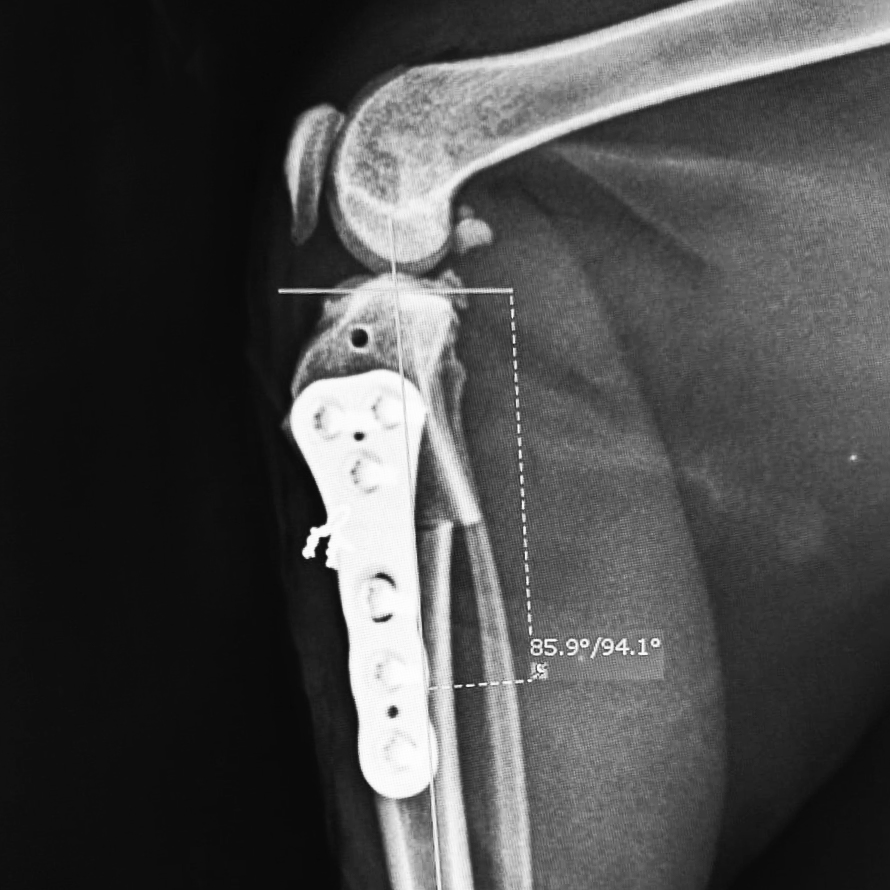

This course will explore the cannulated headless compression screw system, including its design, materials, and surgical applications. Participants will gain insights into the indications for these implants, such as elbow condylar fractures, ununited anconeal process (UAP), and hip procedures.

- Identify appropriate clinical indications for the use of headless compression screws, including elbow condylar fractures, ununited anconeal process (UAP), and hip procedures.

- Demonstrate knowledge of anatomical approaches to the elbow and hip relevant to surgical fixation.

- Apply preoperative planning techniques to optimize surgical outcomes.